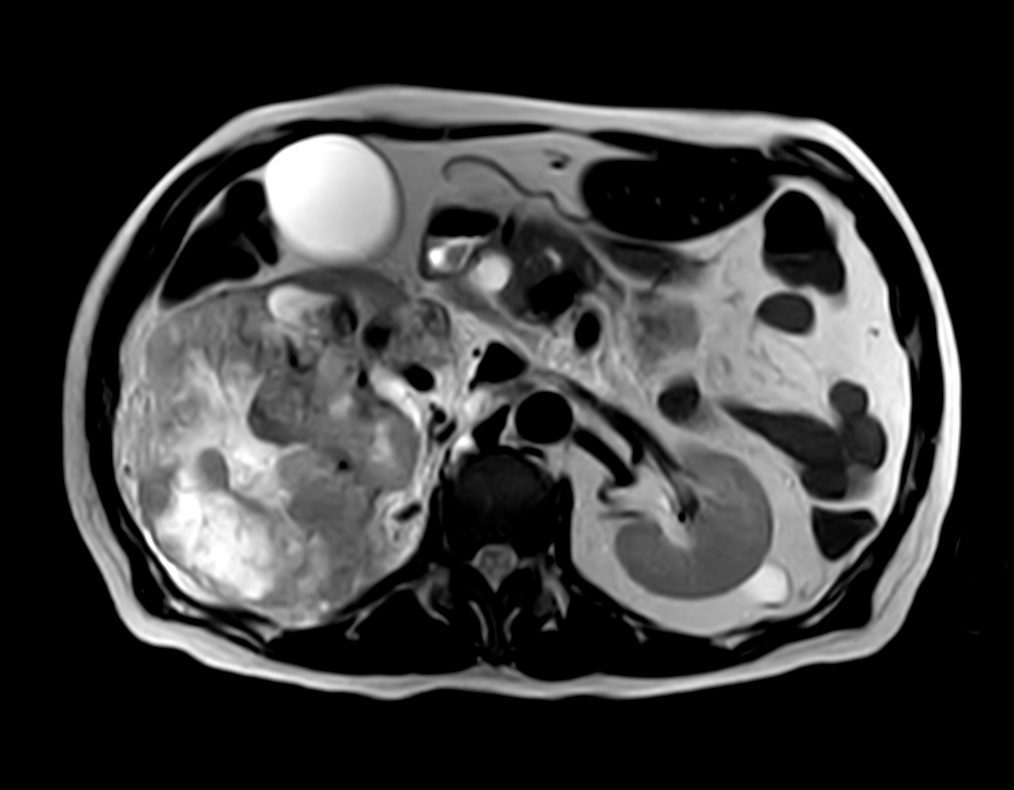

Patient with kidney tumor. ExamCard includes Compressed SENSE to shorten the breath hold time, VitalEye for touchless respiratory sensing, mDIXON XD FFE to acquire up to four image types in one single scan, DWIBS to achieve high contrast between background and lesions and bTRANCE for non-contrast time-resolved imaging.

bTFE - VitalEye Compressed SENSE